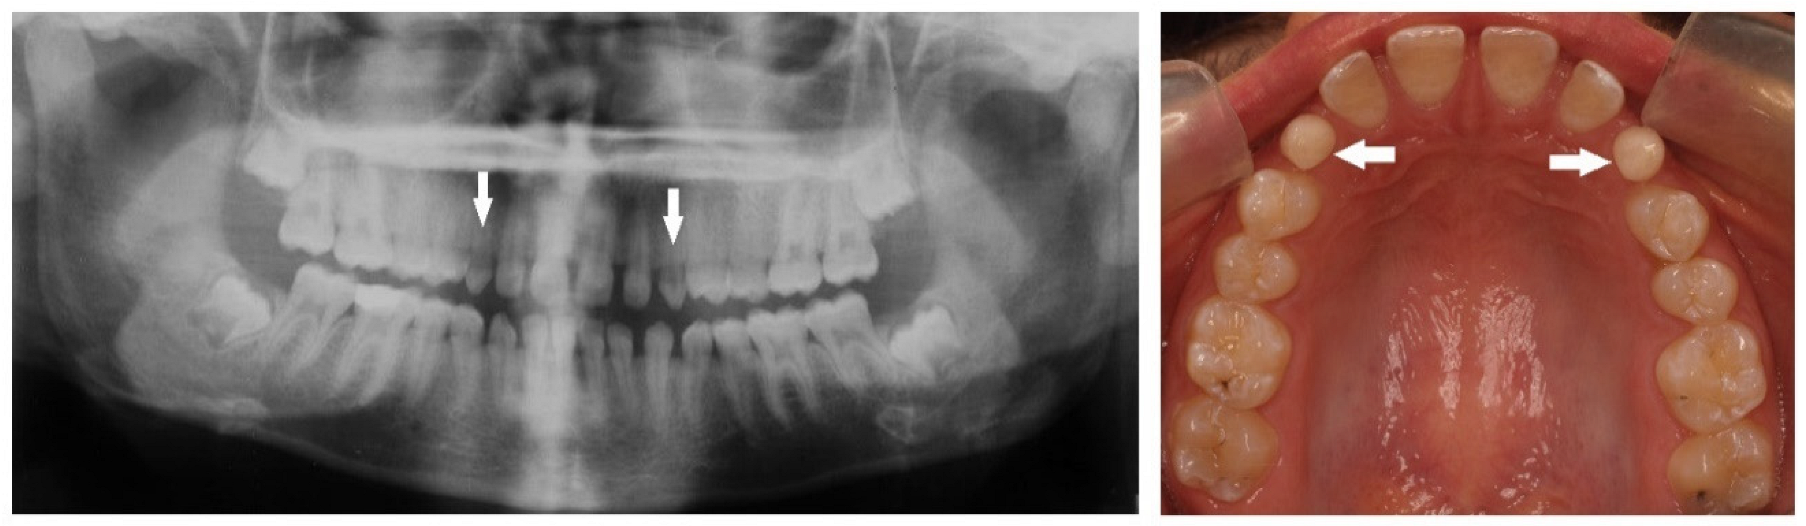

| Peg-shaped | Small conical tooth with a narrowing in diameter from the cervix to the in-cisal edge. |

| Impaction | Failure of tooth eruption into the oral cavity. |